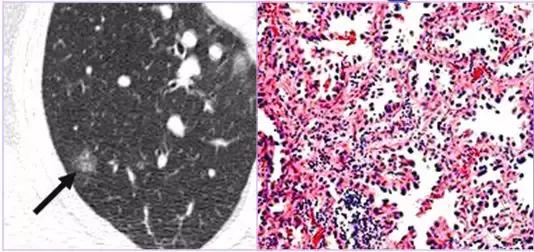

CT征象三:磨玻璃密度影

磨玻璃密度影(GGO):CT表现为肺野低密度背景上略高密度影,边界可清晰也可不清晰,透过其中可显示肺纹理影,有时可见空气支气管征;GGO即可发生在肺间质,也可发生在肺实质病变;预示可能为病变早期。

完全型GGO:恶性占71.4%(其他可能为腺瘤样增生等)

混合型GGO:恶性占93.3%

反映了肺气腔不完全充盈或轻度肺间质的增厚等改变

完全型GGO 混合型GGO

完全型(pGGO)——肺腺癌

完全型(pGGO)——非典型腺瘤样增生

GGO —外伤;GGO—肺间质纤维化